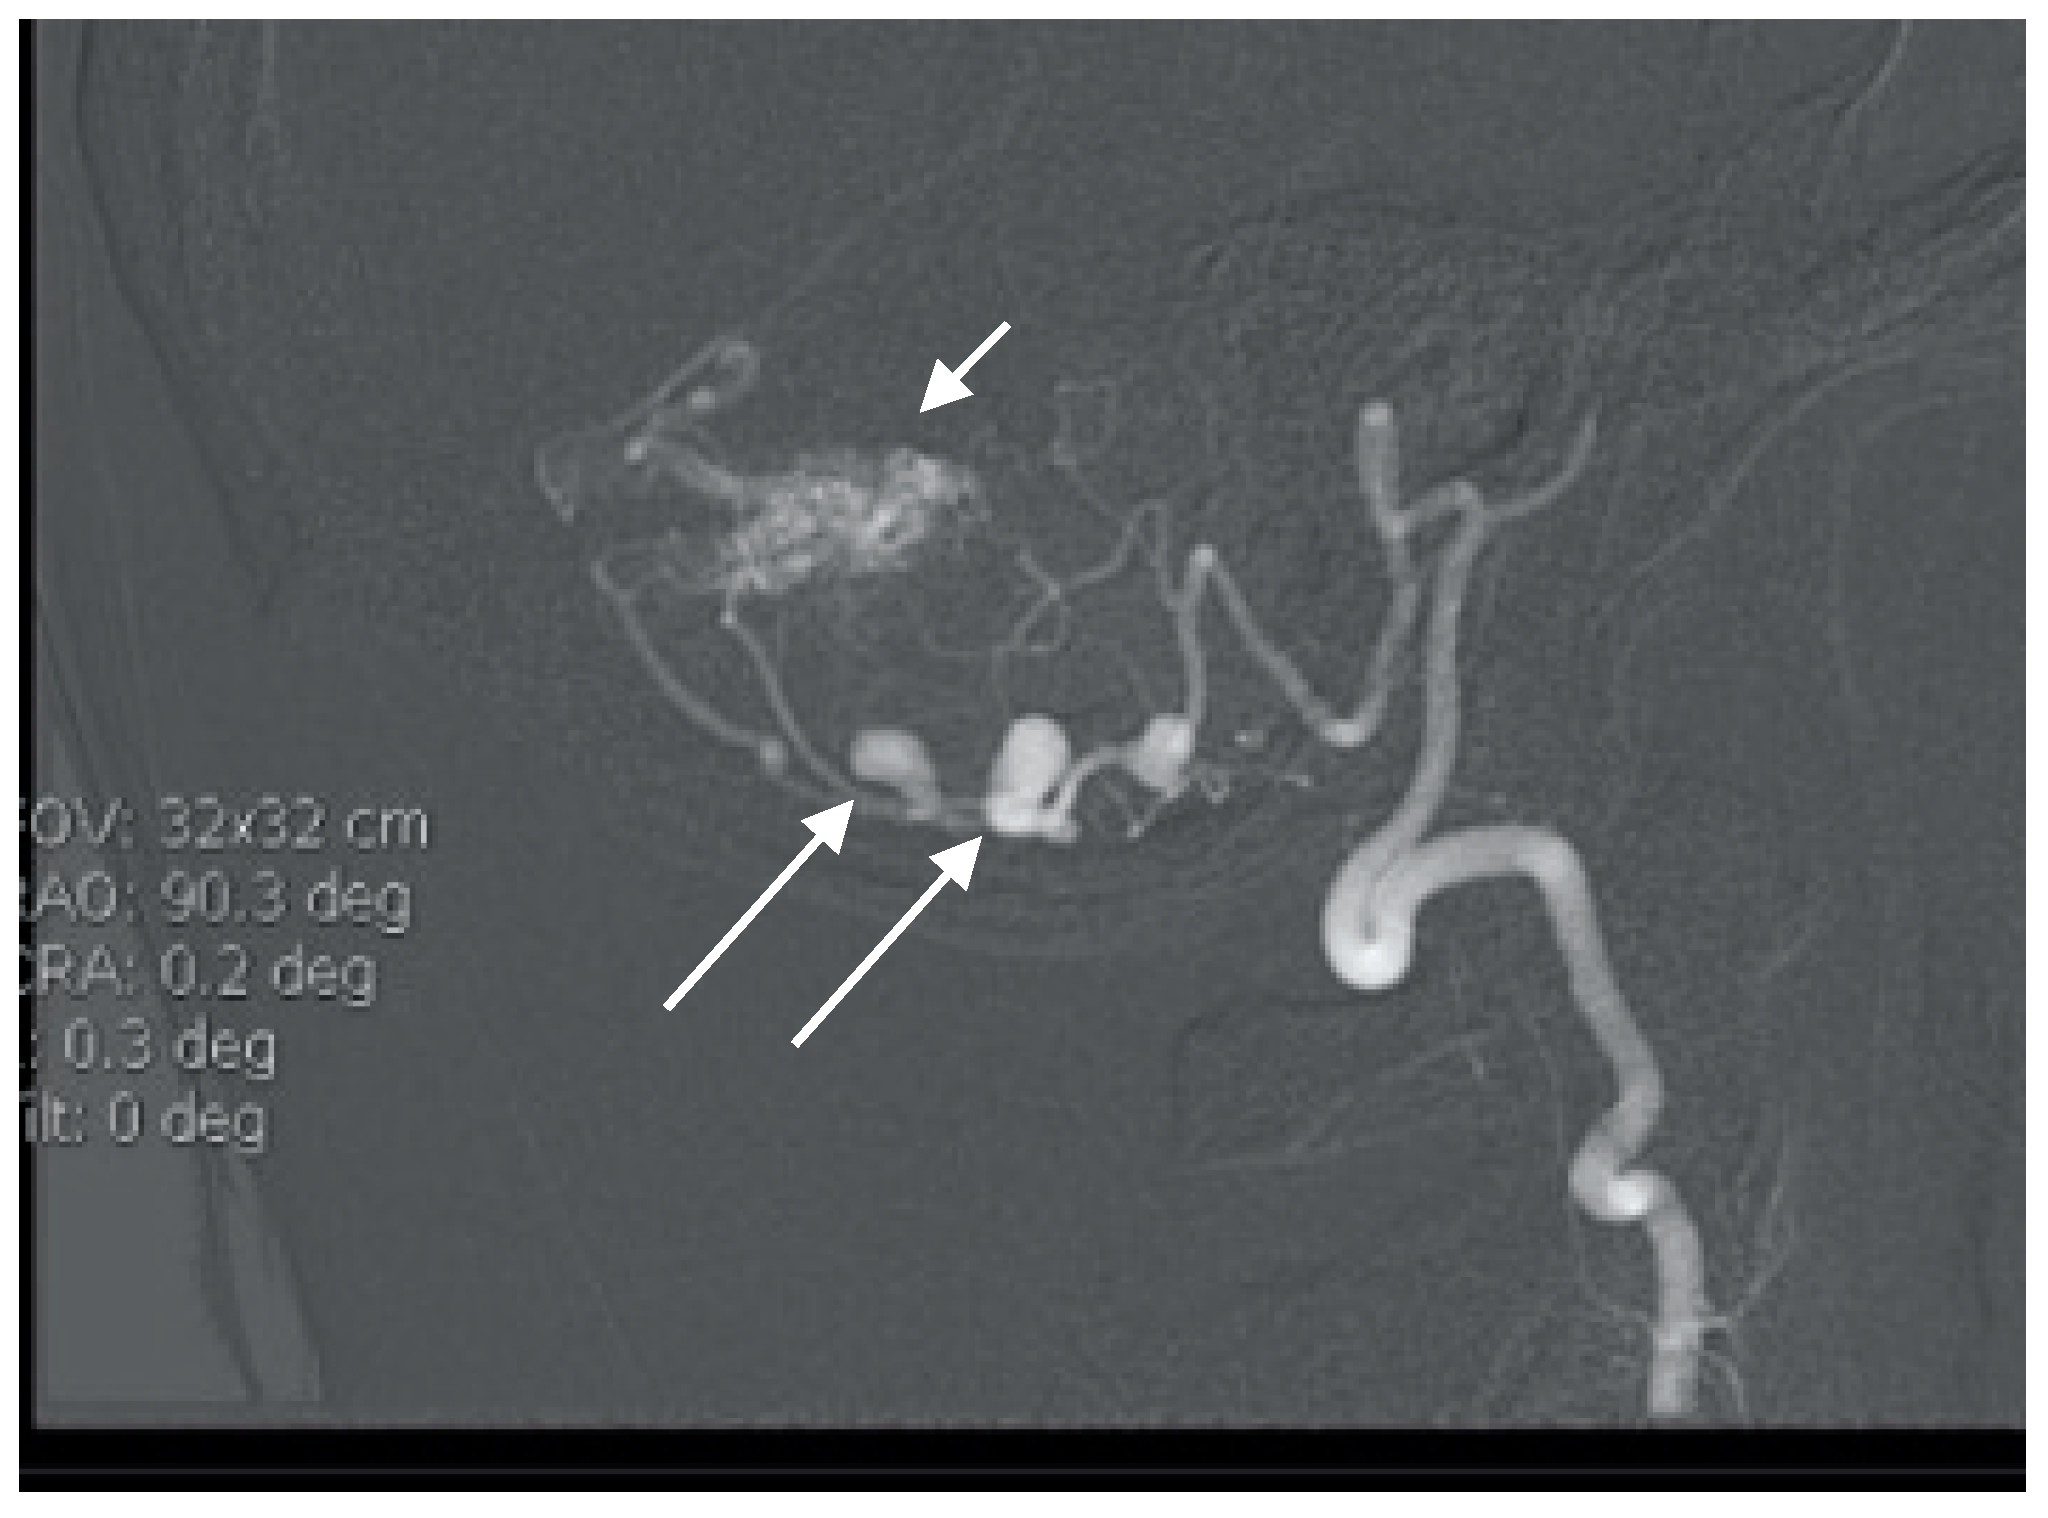

A 52-year-old woman presented with atypical headaches on an acute stage. MRI and subsequent PAG revealed an AVM of the cerebellar convexity with three aneurysms on parent arteries at the SCA and AICA bifurcations (Figure 3). The patient was treated by microsurgical clipping and resection of the AVM. Her postoperative course was uneventful, and follow-ups are undertaken every year.

Figure 3. Multiple superior cerebellar artery (SCA) and AICA aneurysms along with cortical arteriovenous malformation (AVM) of the cerebellum on lateral angiogram highlighted with arrows.